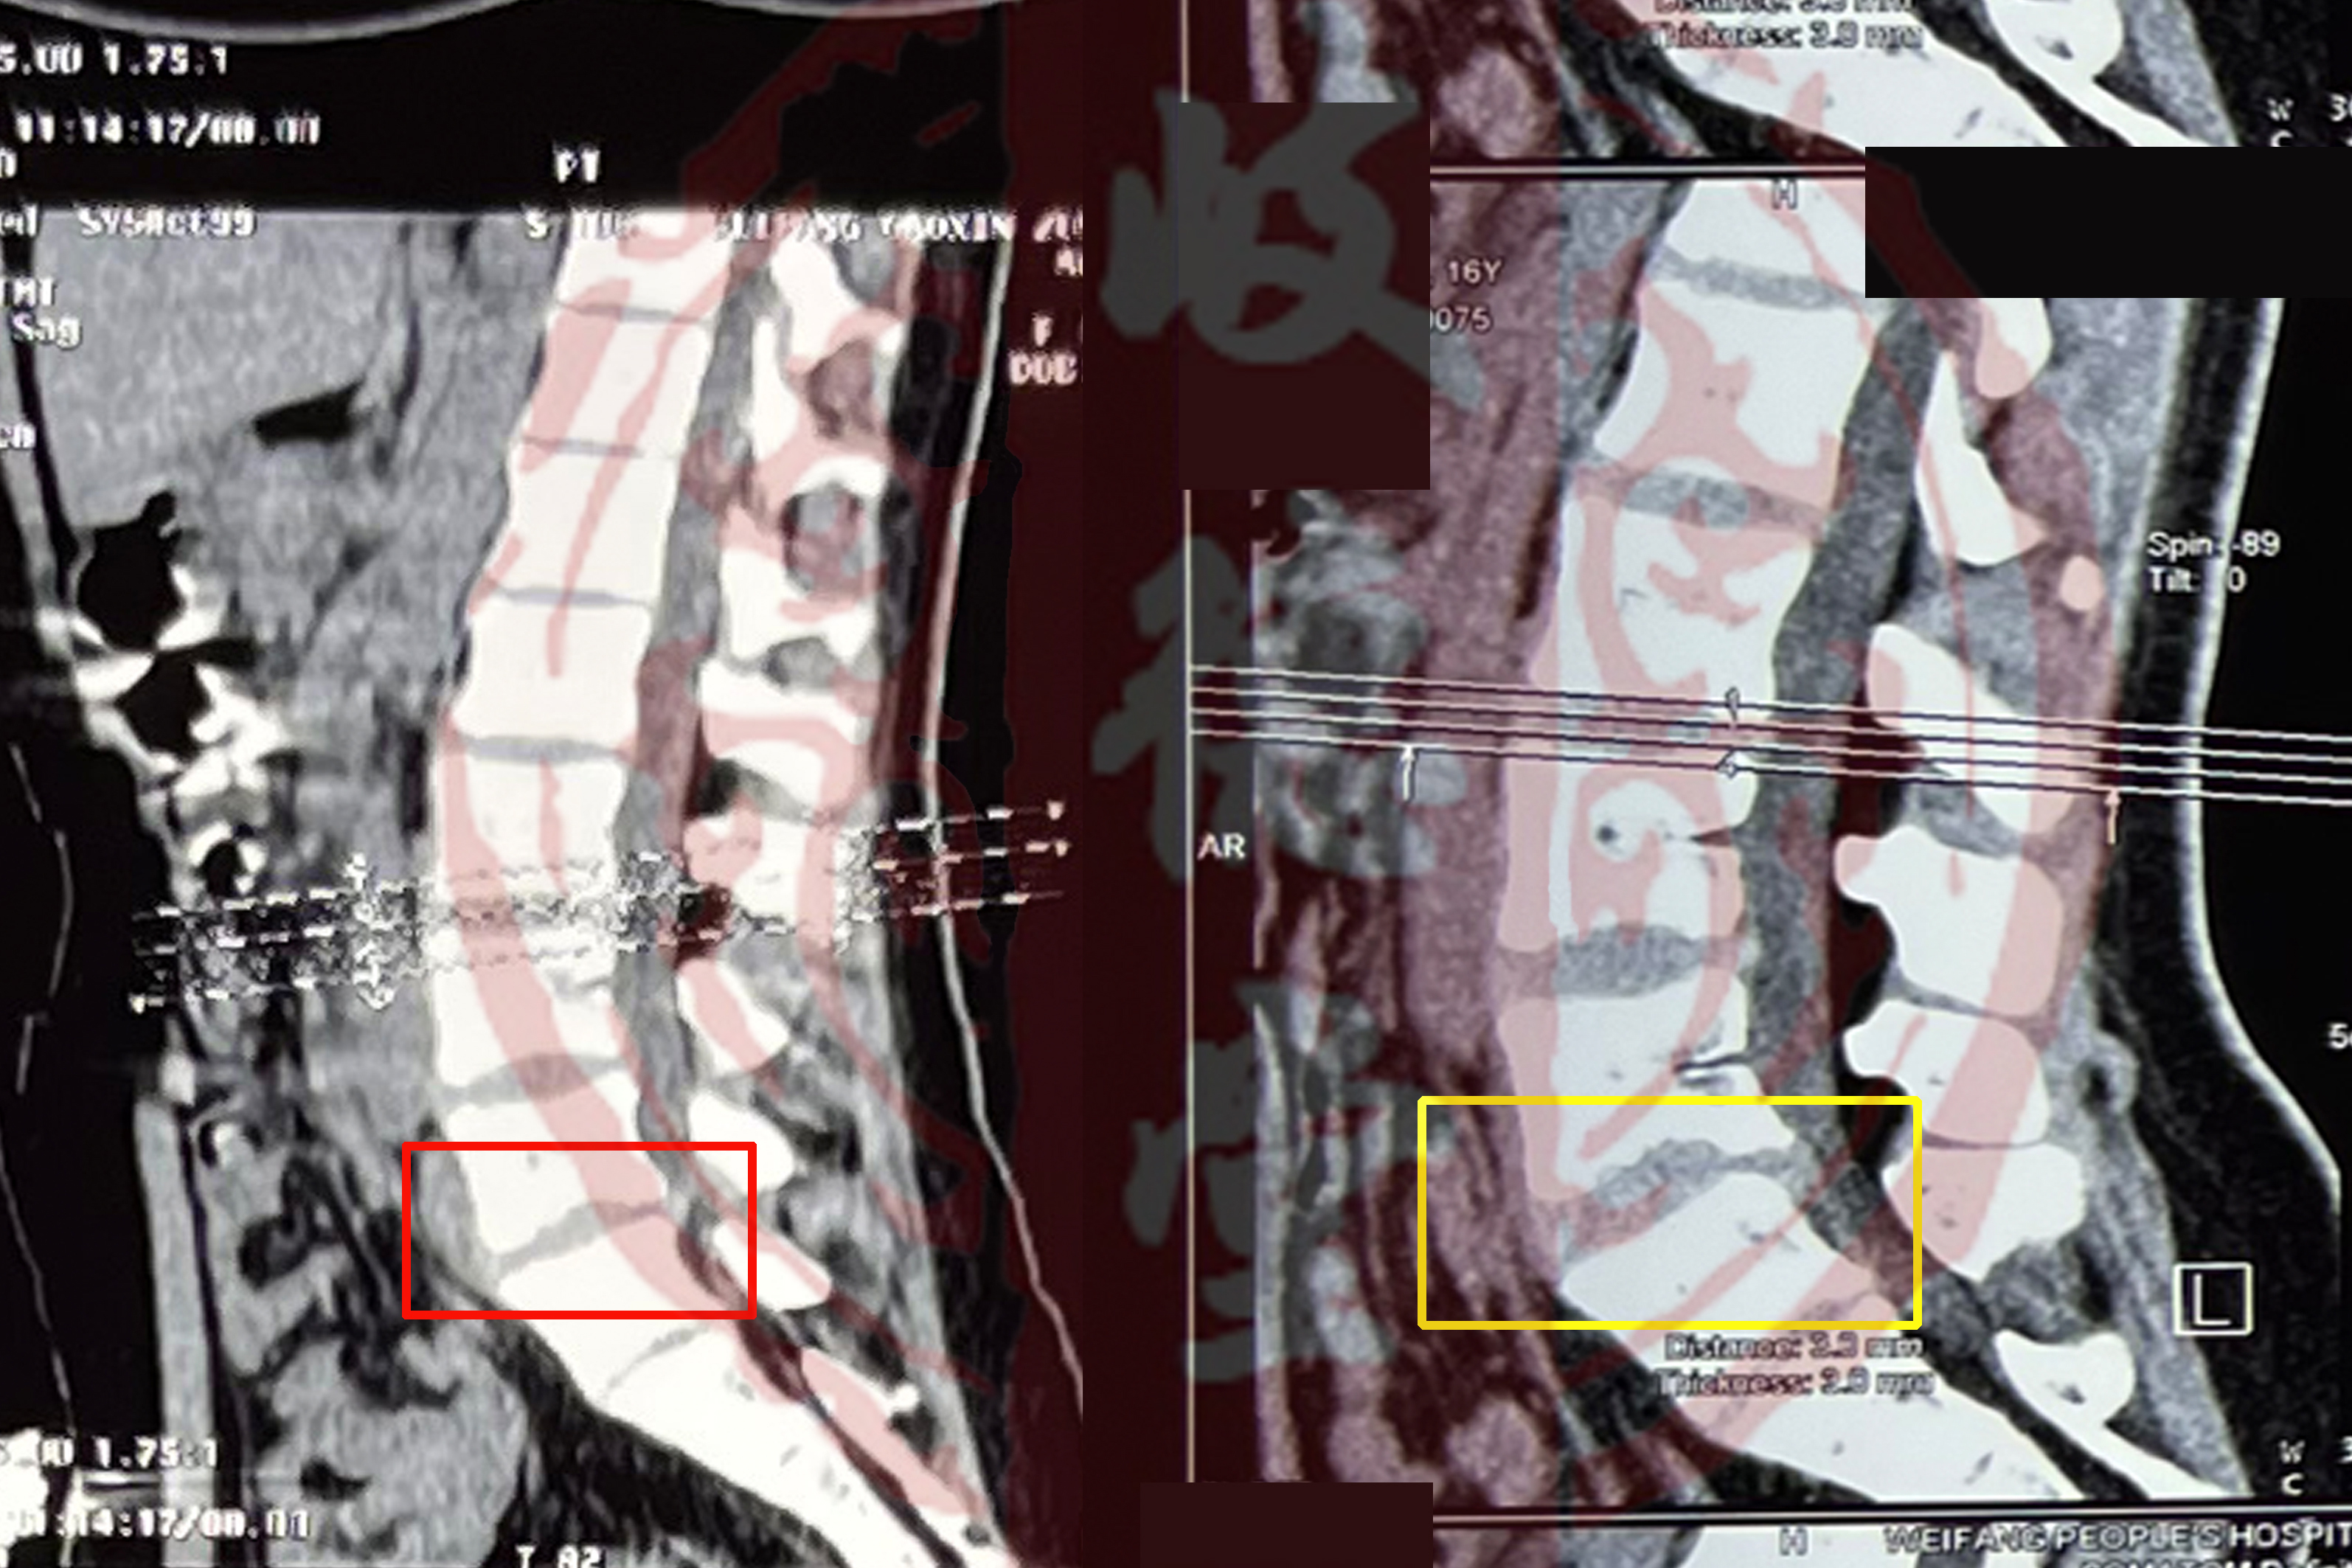

下图案例是一名16岁女性患者的影像片,拍摄时她还没有在岐德堂中医骨科接受治疗,如下图:

上图中方框中标记放大的部分是她病情最严重的位置,已经出现了腰椎滑脱。。